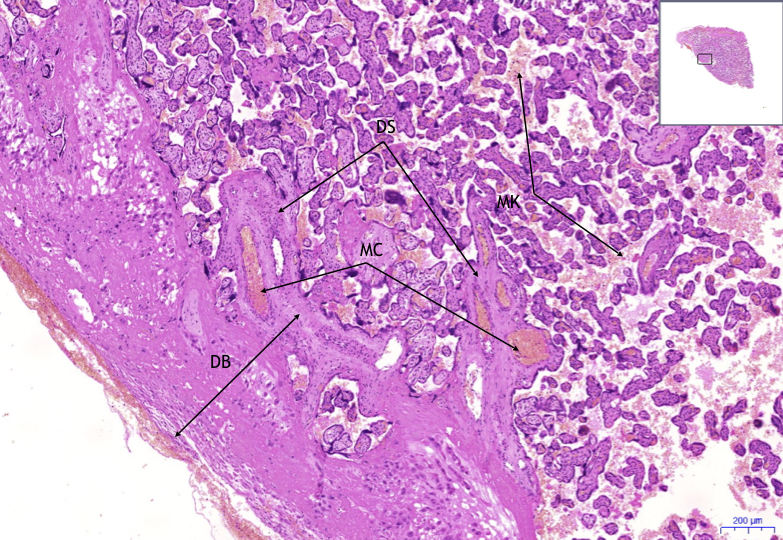

Некробиоз децидуальная ткань что это такое - фото презентация